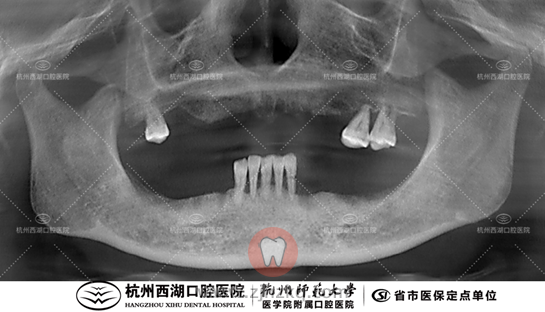

术前CBCT照如下

种植团队采用All-on-6即刻修复技术,为王阿姨上颌下颌分别植入6颗种植体,即日戴牙完成全口修复。

术后CBCT照如下